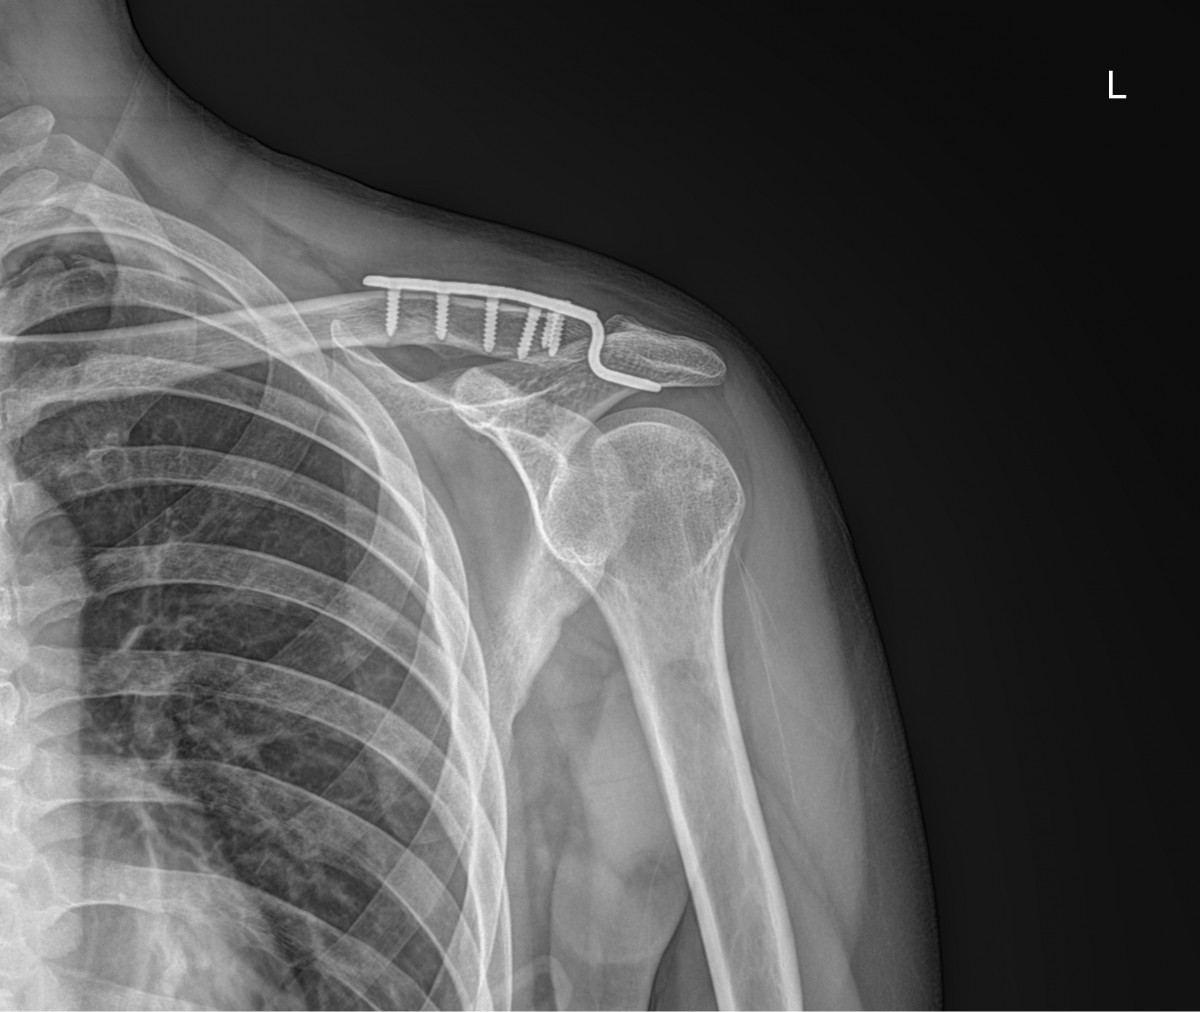

이재상원장님 어깨 골절 수술 김시O 환자

dae765e4d9ac96aee867c9d6292d8784_1758001797_6833.jpg